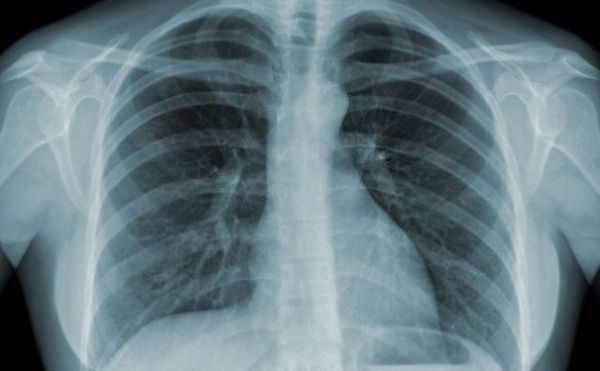

Bệnh phổi tắc nghẽn mạn tính (COPD) trên x quang

Các triệu chứng phổ biến nhất của COPD là khó thở, sản xuất đờm quá mức, và ho mãn tính. Hình ảnh trên phim chụp x quang ngực gợi ý chẩn đoán bệnh phổi tắc nghẽn mạn tính (COPD). Để hiểu rõ về hội chứng này mời các bạn cùng tham khảo bài viết Bệnh phổi tắc nghẽn mạn tính (COPD) trên x quang.

Bệnh phổi tắc nghẽn mạn tính (COPD) không phải là một bệnh duy nhất mà là một thuật ngữ chung dùng để mô tả các bệnh phổi mạn tính gây ra những hạn chế trong luồng không khí phổi. Viêm phế quản mãn tính, giãn phế nang - thuật ngữ quen thuộc hơn và tràn khí không còn được sử dụng, bây giờ được chẩn đoán COPD.